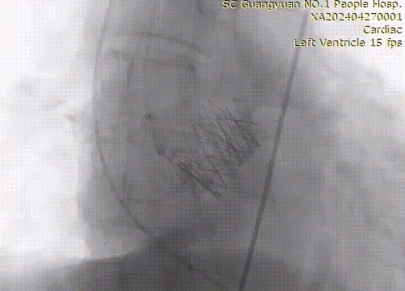

术后造影

术后造影检查显示,瓣膜放置恰到好处,血流通畅、血压改善,显著解决了主动脉瓣狭窄问题,达到术前预期效果。第二天,患者即可下床正常行走。